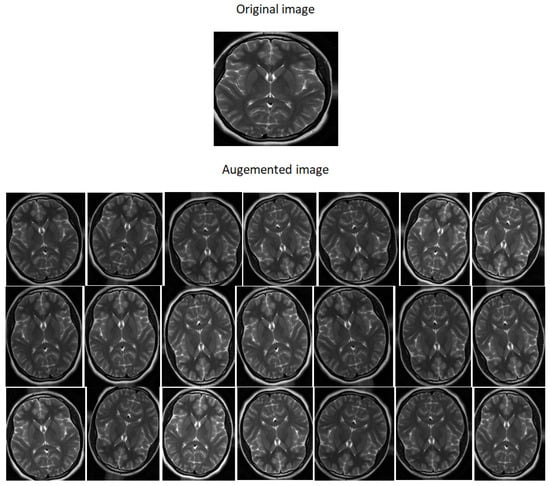

- Dataset generation and expanding an existing dataset (Figure 5)

- Flipping: creates a mirror reflection of an original image,

- Rotation: rotating an image by an angle around the center pixel,

- Translation: involves moving the image along the X or Y direction or both.